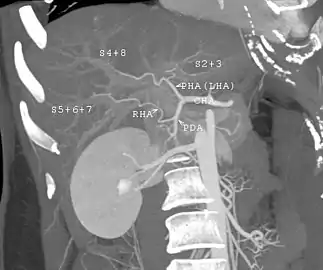

Contrast enhanced MRA of the abdominal aorta demonstrating normal paired arteries.

Contrast enhanced MRA of the abdominal aorta demonstrating normal paired arteries. The celiac artery and its branches; the stomach has been raised and the peritoneum removed.